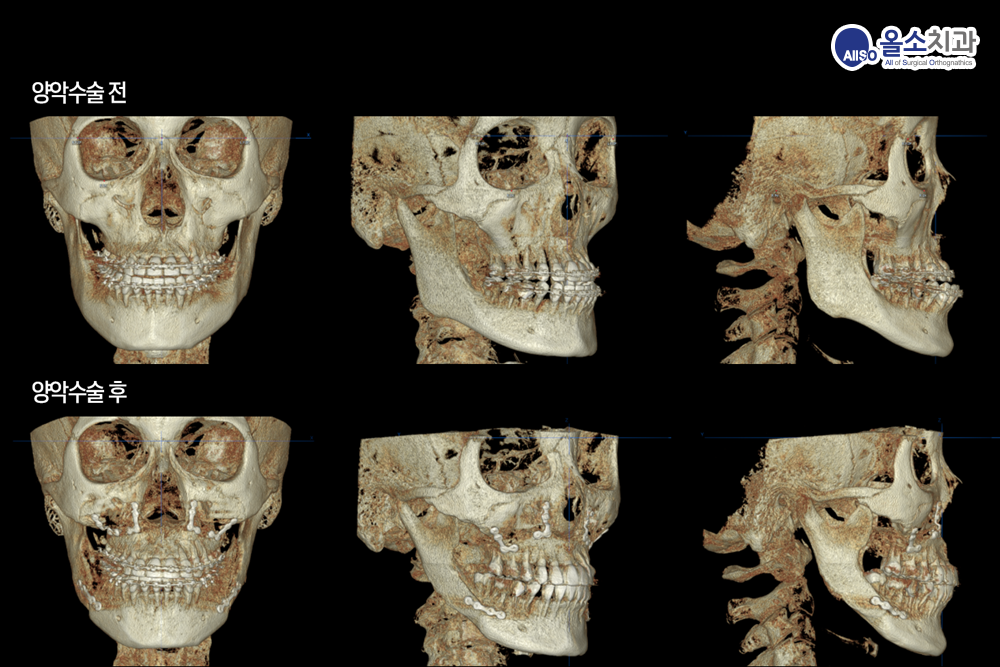

3d.png

3D 분석을 통해서 주걱턱과 비대칭의 양이 정확하게 측정되고, 이를 바탕으로 수술 계획이 세워집니다.

3D 기술을 이용하여 수술 전후 변화를 3차원적으로 확인할 수 있습니다. 비대칭과 주걱턱이 한번의 수술로 정확하게 고쳐졌음을 알 수 있습니다.